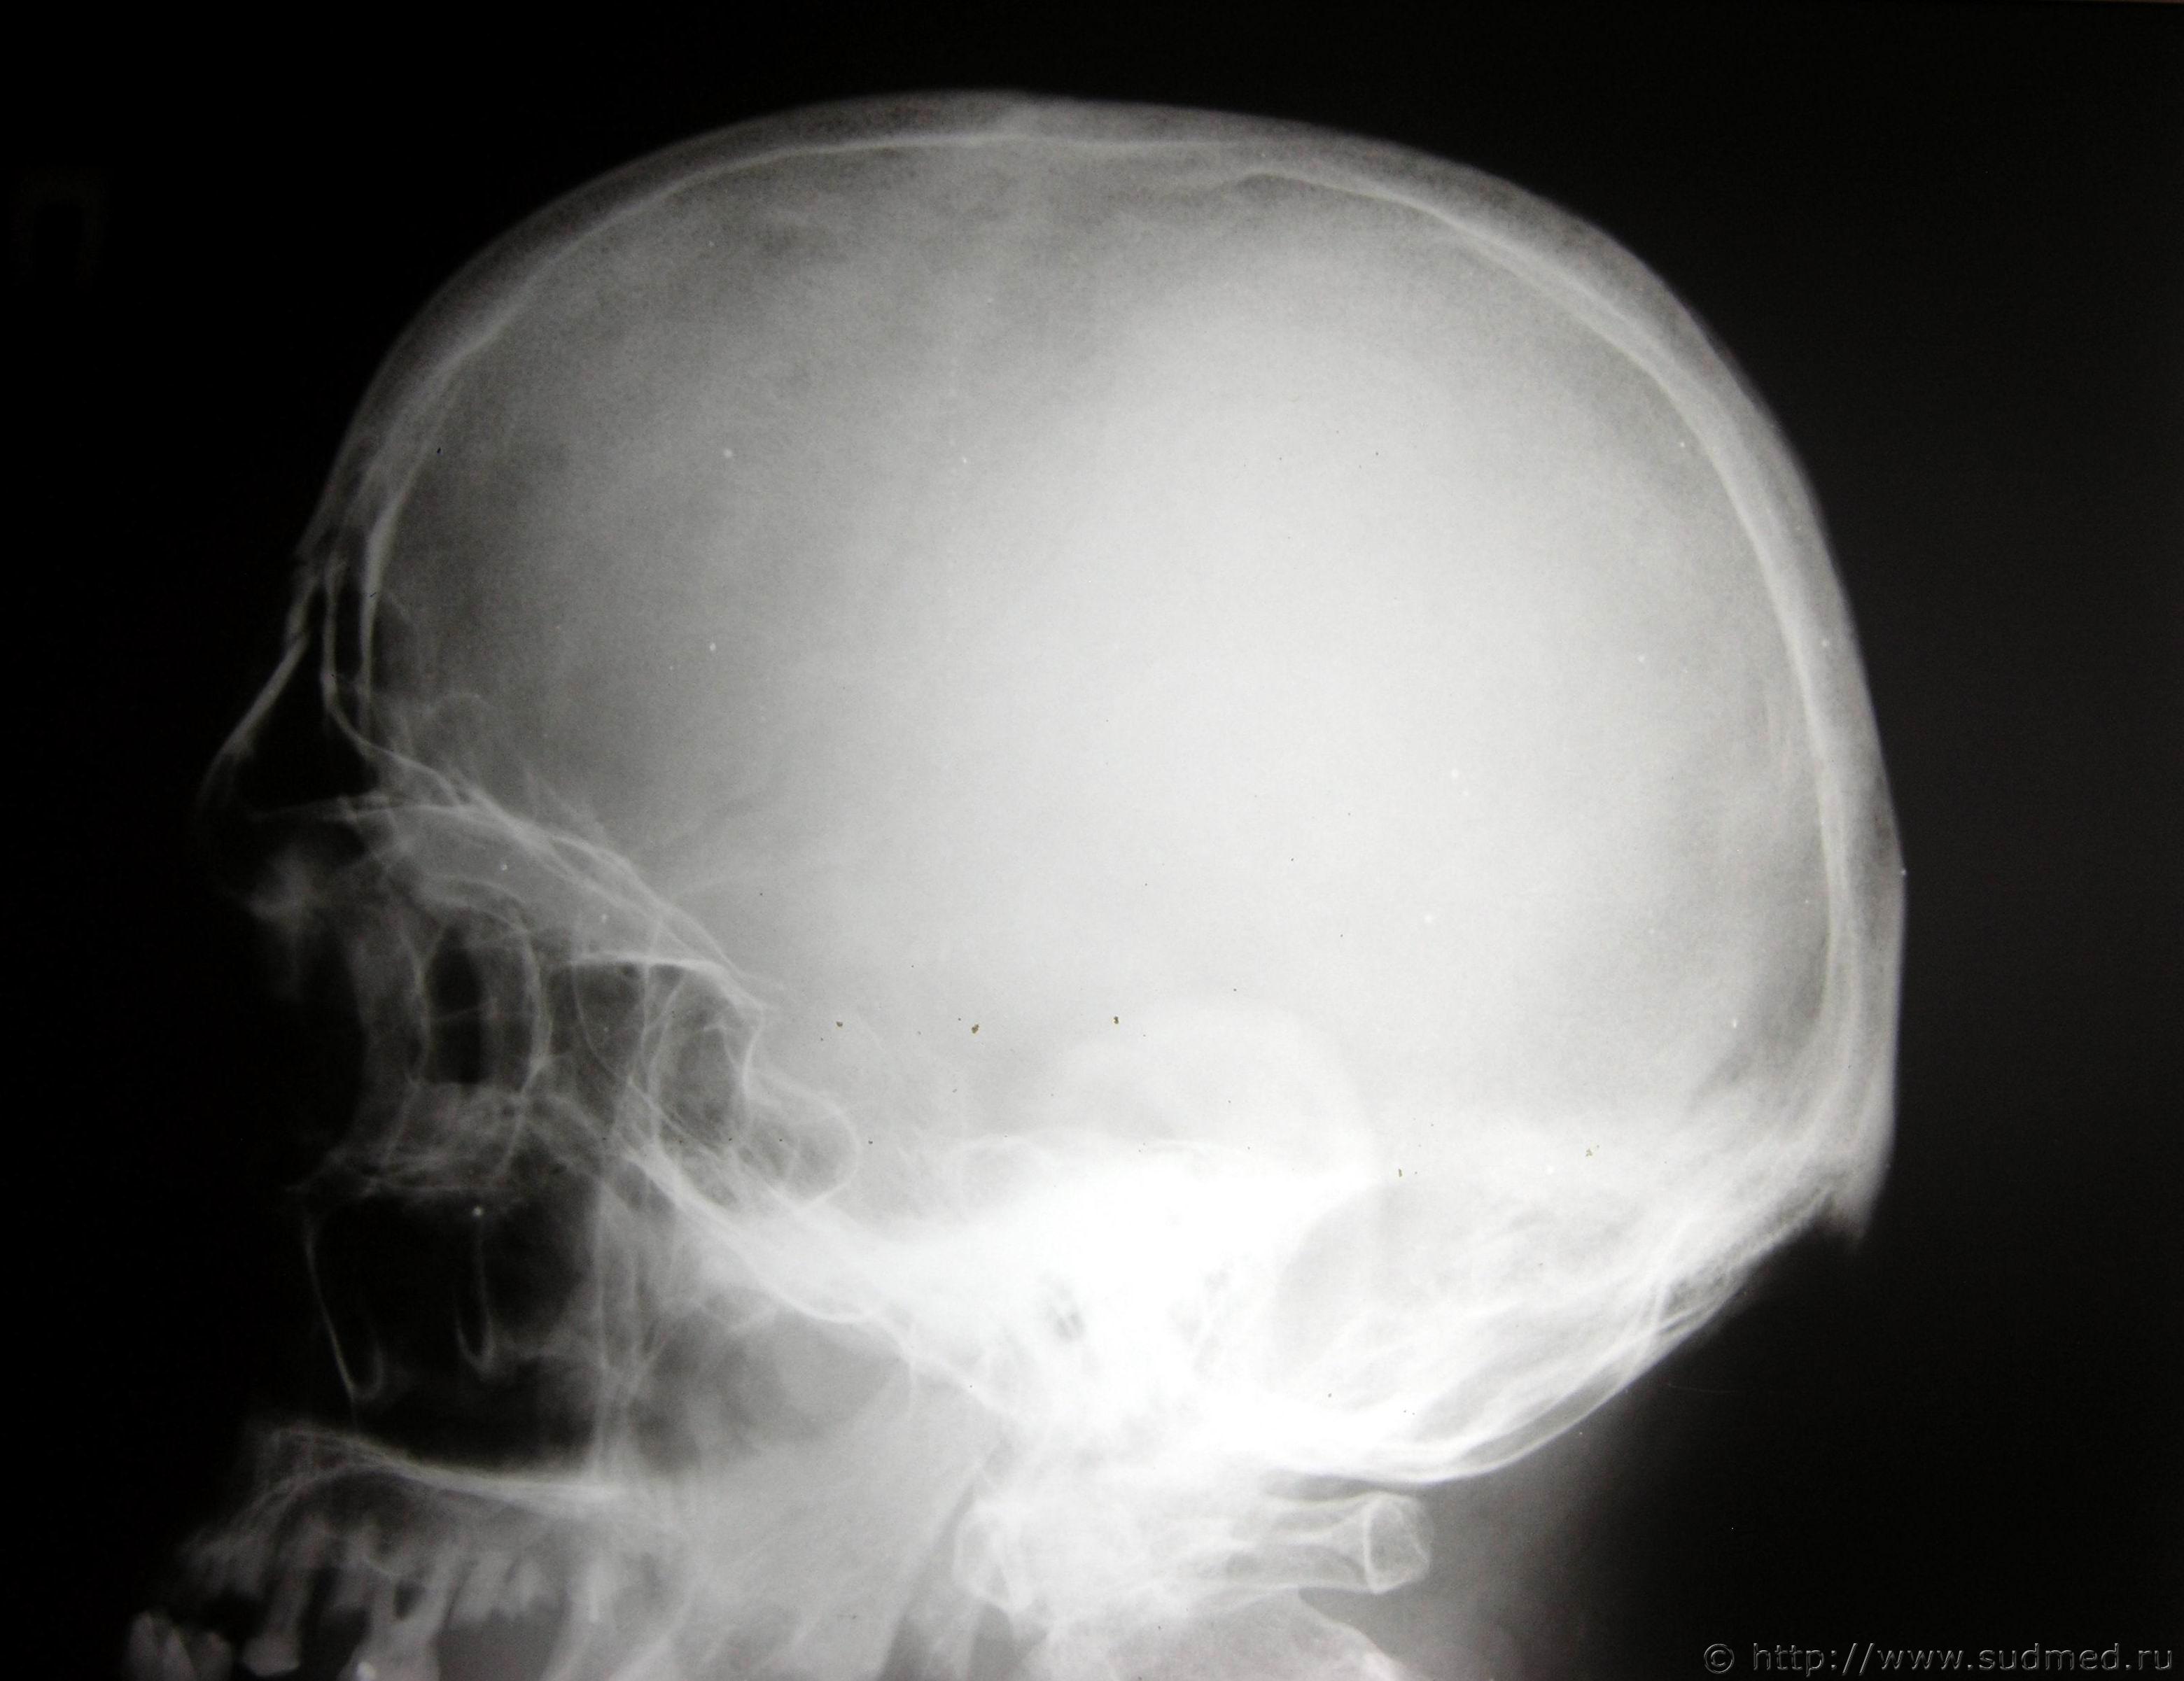

У мужчины 55 лет были обнаружены телесные повреждения: "...В лобной области определяется ушибленная рана с неровными краями, ослизнена..." На На рентгенограммах черепа в 2-х проекциях от 09.02.2016г. №... определяется перелом лобной кости в боковой проекции.

Согласно п. 6.1.2 ... перелом лобной кости квалифицируется как тяжкий вред. Исключения составляют переломы лицевых косте и изолированные переломы наружной костной пластинки... В комментариях указывается, что в эту группу включаются все переломы внутренней костной пластинки. Как видно на рентгенограммах в данном случае внутренняя костная пластинка не повреждена. Но ни в критериях, ни в комментариях про переломы лобной пазухи ни чего не сказано.

ВОПРОС: Как по Вашему мнению подойти к квалификации степени тяжести вреда здоровью в данном случае - как к перелому лобной кости и, соответственно, тогда тяжкий вред или при не поврежденной внутренней костной пластинке свода черепа по длительности расстройства здоровья и тогда средний?

Как видно на рентгенограммах в данном случае внутренняя костная пластинка не повреждена.

ну и в чем тогда проблема? По длительности тяжесть